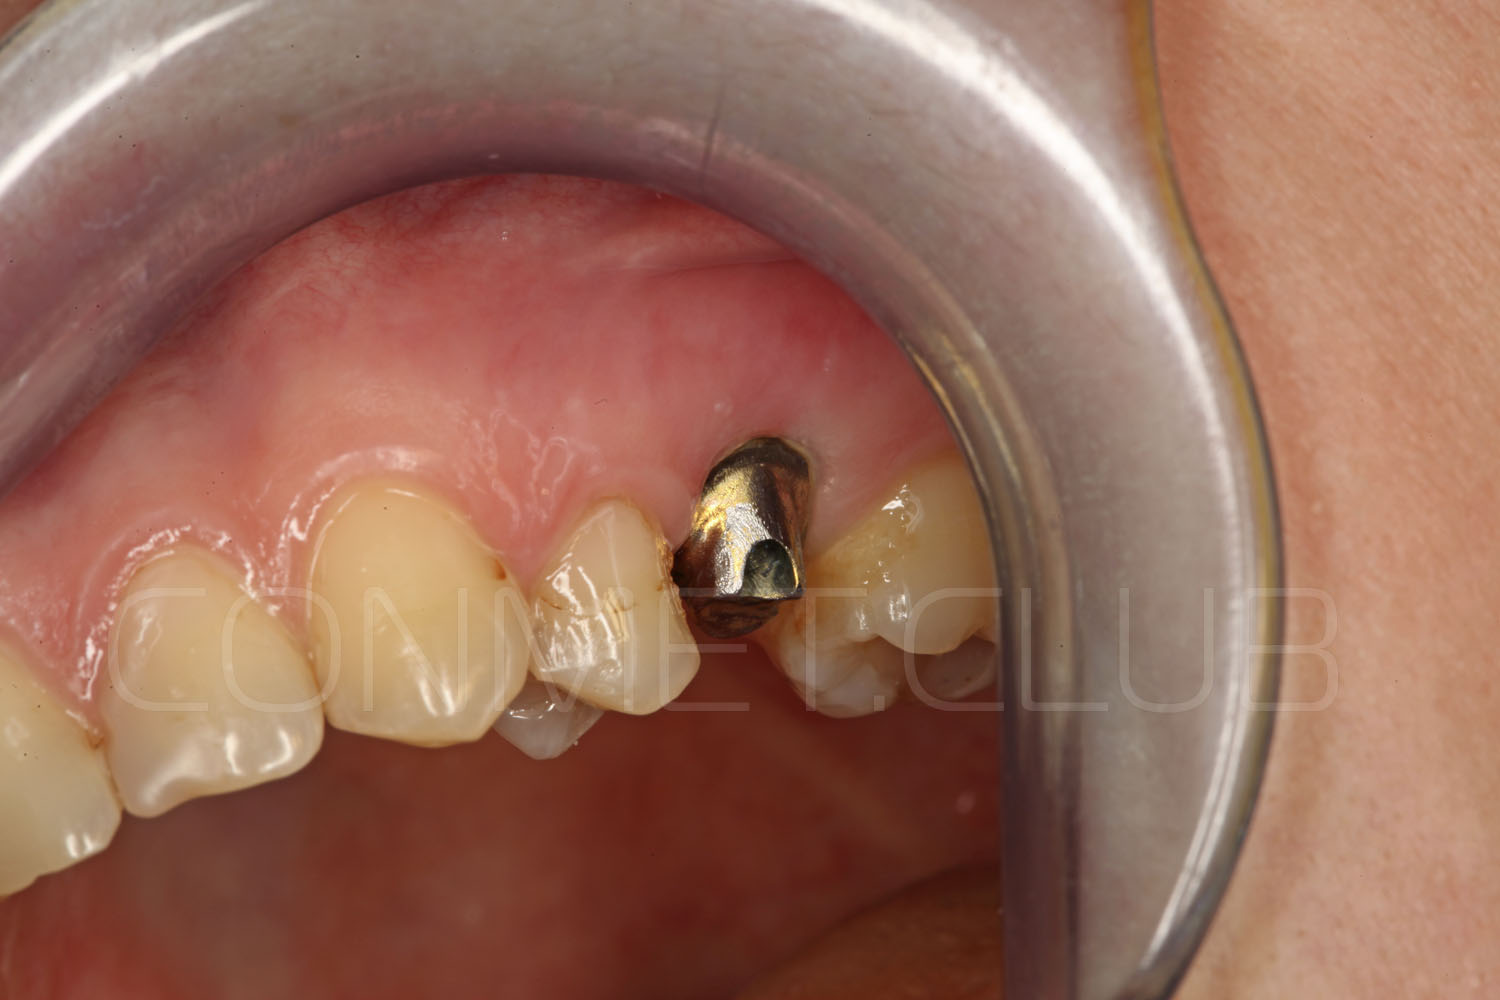

Вид в полости рта пациента перед операцией. С момента удаления зуба 25 прошло 4 месяца. Планируется проведение операции без откидывания слизисто-надкостничного лоскута.